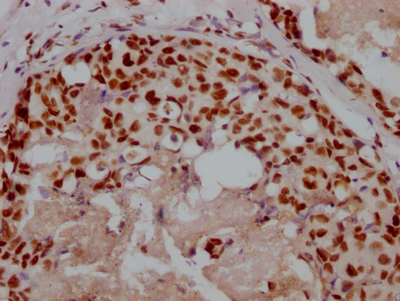

Immunofluorescent analysis of Hela cells using CSB-PA896901LA01HU at dilution of 1:100 and Alexa Fluor 488-congugated AffiniPure Goat Anti-Rabbit IgG(H+L)